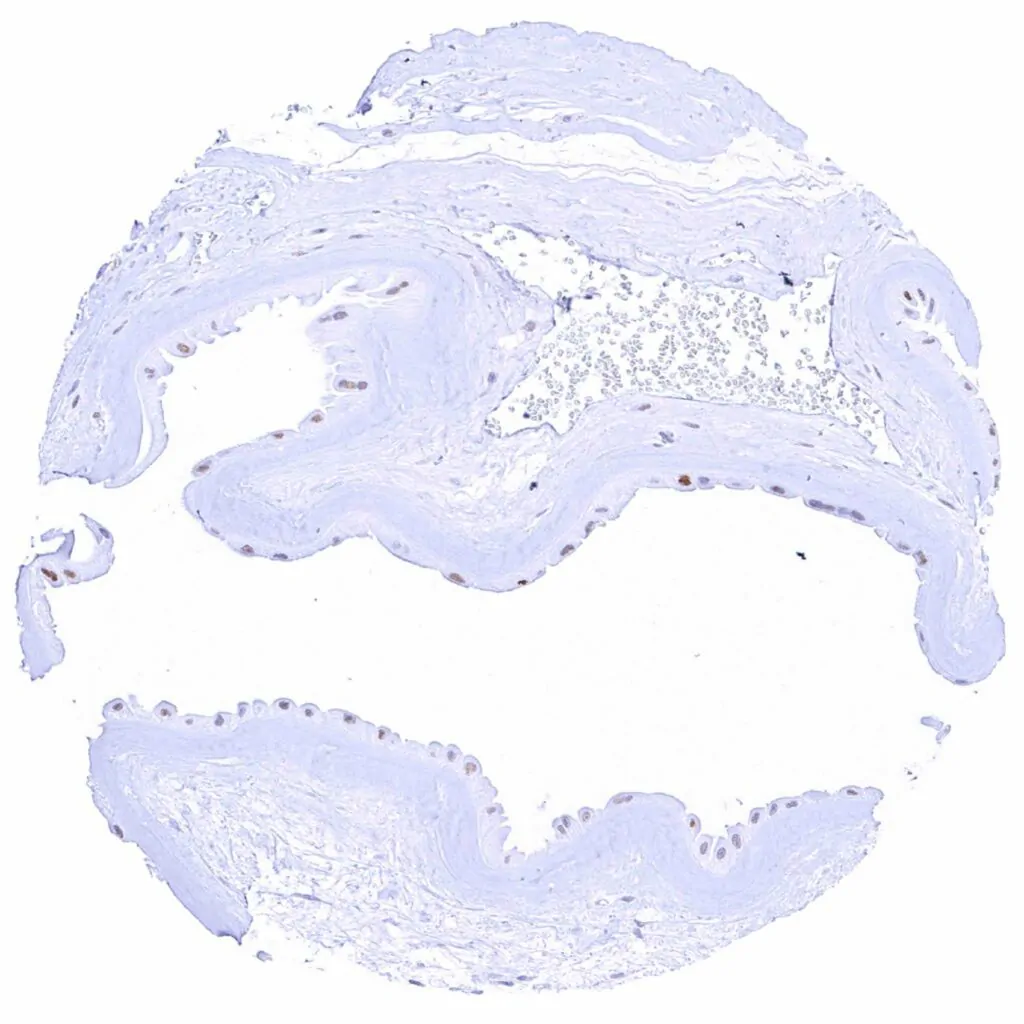

Kidney, pelvis, urothelium – Weak to strong Cyclin E1 staining of urothelial cells is limited to the top cell layers of the urothelium. The staining intensity increases towards the surface

Skin – Weak to strong Cyclin E1 staining of squamous epithelial cells of the upper half of the epidermis. The staining intensity gradually increases towards the surface

Tonsil, surface epithelium – Strong Cyclin E1 staining of most squamous epithelial cells in the upper half of the surface epithelium

Esophagus, squamous epithelium Weak to strong nuclear Cyclin E1 staining of squamous epithelial cells in the upper half of the surface epithelium. The staining intensity gradually increases towards the surface